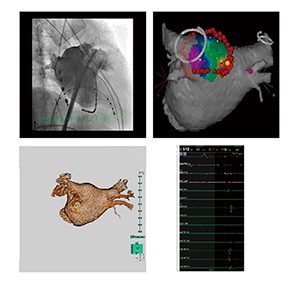

■不整脈関係の画像

検査マッピングや波形などの画象はDICOM形式ではないものが多い。これらの画像を撮影画像と同様にサーバ管理できるようにした(図2)。これにより,検査全体の画像を電子カルテなどで一括レビューできるようになった。

図2 不整脈画像のサーバ管理